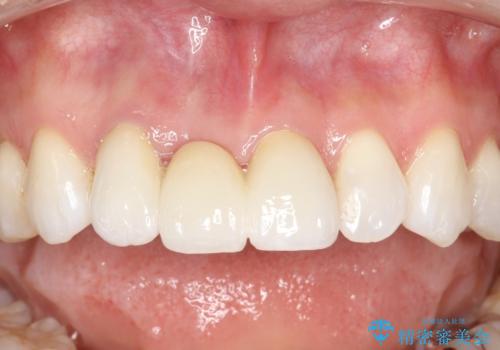

前歯がぐらぐらする 抜歯→ブリッジへ

古いかぶせ物は土台ごと歯から脱落してしまっており、歯の内面には複数の亀裂が入っている状態でした。残存歯質が非箔であることと、動揺の程度から、やむを得ず抜歯→ブリッジという方法を選択していただき、歯根挺出を用いることでなるべく前歯の骨の陥没を防ぎ、ブリッジを製作しました。

かぶせ物の種類:PFZ standard